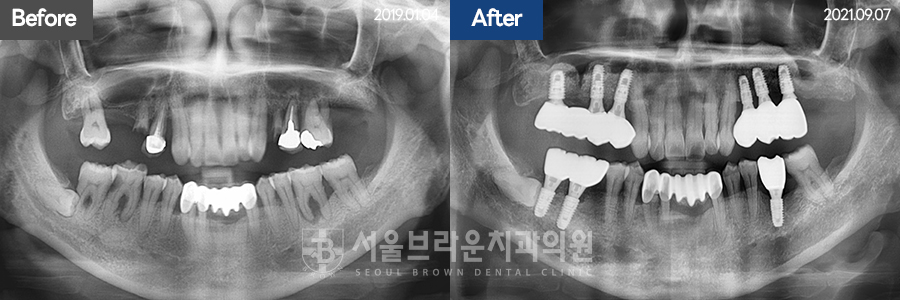

임플란트 | 50대 / 여 / 상하악임플란트

50대 / 여 / 상하악임플란트